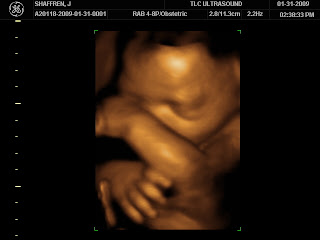

Ella in 3D/4D

Yesterday we went to get a 3d/4d ultrasound! It was truly incredible. We brought both sides of the family with us for this viewing spectacular. Ella was beautiful but kept wanting to keep her hands and feet in front of her face, what an acrobat!! She also was a little sleepy, she kept yawning (it was so cute!). Anyway, here are some pics from the event. Enjoy! :)